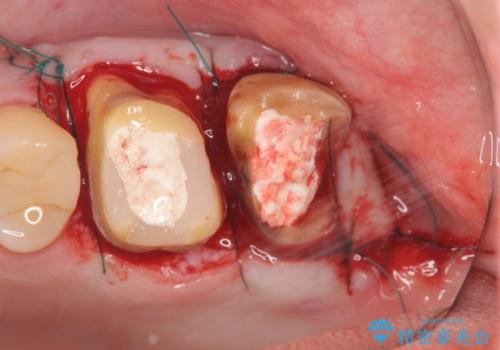

・深い虫歯 →歯周外科を行うことで歯ぐきの腫れを改善

・根尖性歯周炎 →精密根管治療

と問題点を一つづつ丁寧に解決し、長期的に虫歯が再発せず安定を見込める治療を行っていきます。